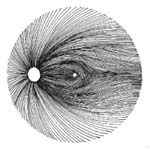

Modrá šipka - ukazuje plochu na sítnici, která obsahuje nervová vlákna. Sítnice je jemně proužkovaná, světlejší, cévy "jsou jako pod závojem". Červená šipka - ukazuje místo bez nervových vláken. Sítnice je tmavší, bez proužkování. Cévy jsou ohraničeny neobvykle ostře.